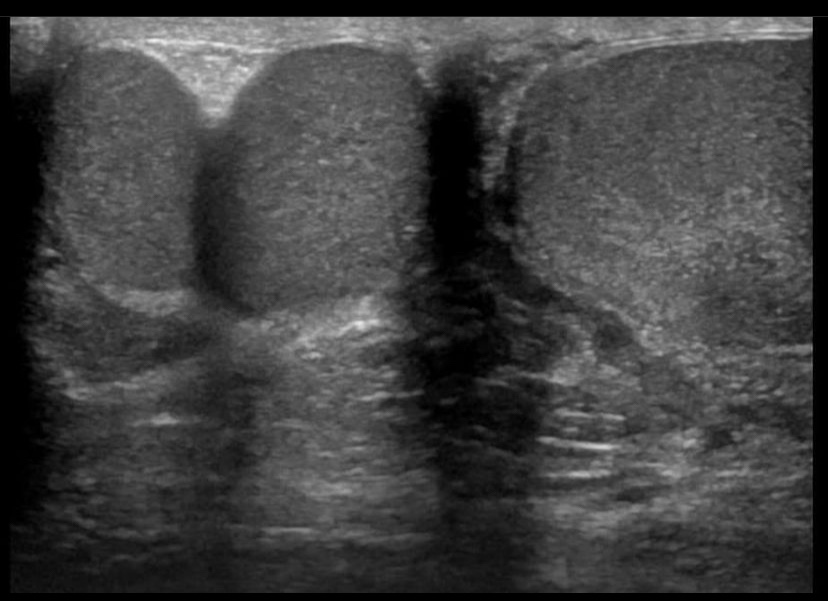

Polyorchidism or supernumerary testicles is a rare condition with the presence of an accessory testis, can be unilateral or bilateral. It is believed to occur due to abnormal development of the genital ridge in the 8th week of fetal development.

75% of cases represent as a painless palpable mass in the scrotum. [1]

Thereis usually 3 testes with the extra testicle usually located in the LT in 64.5 % of cases. [2]

Leung [3] and Singer and colleagues [4] classified embryonic polyorchidism into four types.

- Type A: Supernumerary testicle lacks an epididymis and vas deferens.

- Type B: Supernumerary testicle shares an epididymis and vas deferens with another testicle.

- Type C: Supernumerary testicle has its own epididymis and shares the vas deferens with a regular testicle.

- Type D: The supernumerary testicle has complete duplication of testicles, epididymides and vas deferens.